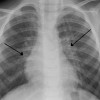

Izin tanya dok. Bayi 20 bulan mengalami cekungan di kosta kanan ke 7 dan 8, cekungan terlihat di perbatasan kartilago dan kosta terutama saat tarik nafas dalam. Tidak ada gejala lain yang dirasakan, pertumbuhan dan perkembangan sesuai usia.

Ijin Dokter, jika dilihat bahwa retraksi ini dilihat ipsilateral, dipikirkan terlebih dahulu apakah ada trauma sebelumnya. Jika retraksi bilateral, dapat digali adakah tanda/gejala yang mengarah pada infeksi atau sebelumnya pernah mengalami infeksi. Pada anak masih dapat dipikirkan beberapa diagnosis, seperti bronkiolitis, pneumonia, trauma costae (apabila terdapat riwayat trauma). Semoga membantu.